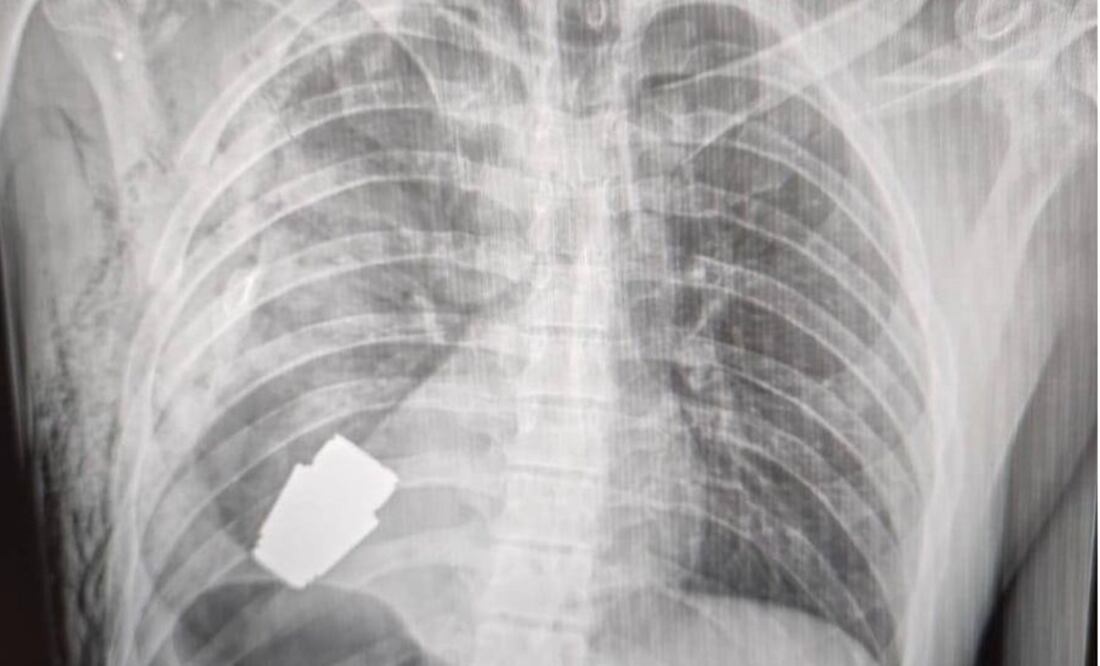

El resultado de la delicada operación fue dado a conocer por la viceministra de Defensa, Hanna Maliar, quien publicó en redes sociales que "no todas las heridas en la zona del corazón son letales".

Agregó que la granada fue extraída bajo la supervisión de dos militares expertos en explosivos para tratar de asegurar la seguridad de los médicos y dar indicaciones para evitar que fuera detonada.

Durante la operación no se pudo utilizar la electrocoagulación, procedimiento común en las cirugías del corazón para evitar que el paciente sufra una hemorragia, por temor a que la corriente eléctrica pudiera detonar la granada.

El fragmento de la granada de fabricación rusa que quedó alojado en el cuerpo del soldado tenía cuatro centímetros de diámetro y pesaba 275 gramos.

Lo que más impresiona a los analistas es cómo la granada permaneció sin detonar pese a mantenerse explosiva durante y después de la operación hasta que fue desactivada por los especialistas